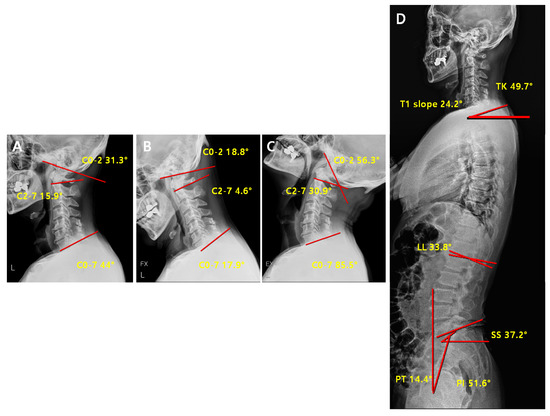

2.3. Radiographic Measurement

| C2-7 Cobb angle | The intersection angle between the line perpendicular to the line parallel to the C2 lower endplate and the line perpendicular to the line parallel to the C7 lower endplate |

| C0-2 Cobb angle | The occipito-cervical angle, which is the intersection angle between the McGregor line and the line parallel to the C2 lower endplate and is used to evaluate the curvature of the upper cervical spine |

| C0-7 Cobb angle | The intersection angle between the McGregor line and the line parallel to the C7 lower endplate |

| T1 slope | The intersection angle between the tangent line and the upper plate of the T1 vertebral body |

| SS (Sacral Slope) | The angle formed by a line drawn along the endplate of the sacrum and a horizontal reference line |

| PT (Pelvic Tilt) | The angle formed by a line drawn from the midpoint of the sacral endplate to the center of the bicoxofemoral axis and a vertical and a vertical plumb line |

| PI (Pelvic incidence) | The angle formed by two vectors: (1) The line joining the bicoxo-femoral axis to the center of the sacral end plate and (2) A line perpendicular to the sacral endplate |